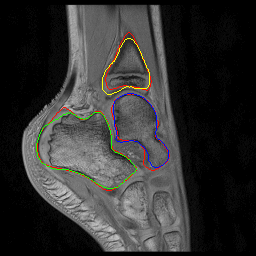

Fig. 2: Visual comparison of UNet regularization methods: baseline UNet [2], adversarial regularization [6], shape priors based regularization [7] and the proposed shape priors based adversarial regularization on ankle dataset. Ground truth delineations are in red (). Predicted bones, calcaneus, talus and tibia respectively appear in green (), blue () and yellow ().

Experiments were conducted on two pediatric datasets previously acquired using a 3T Philips scanner [4]. The two MR images datasets were independently acquired on two musculoskeletal joints (ankle, shoulder) from a cohort of 17 and 15 pediatric patients. An expert (12 years of experience) annotated images to get ground truth contours of calcaneus, talus and tibia for ankle, as well as scapula and humerus for shoulder. All axial slices were downsampled to 256×\times256 pixels.

We compared the proposed shape priors based adversarial regularization method (SPAR in Fig.1) with baseline UNet (Base. UNet) [2], adversarial regularization (Adv. Reg.) [6] and shape priors based regularization (Sh. Reg.) [7]. For all methods, the backbone UNet architecture and all training hyper-parameters remained the same. All networks were trained from scratch with randomly initialized weights.

From the quantitative results (Tab.1), our method achieved competitive results compared to state-of-the-art on both datasets. On ankle dataset, our approach ranked best in Dice (92.7%percent\%), RAVD (8.0%percent\%), ASSD (0.8mm) and MSSD (8.1mm) metrics. For shoulder dataset, our method outperformed other approaches in RAVD (13.6%percent\%) while remaining second best in Dice (0.3%percent\% lower than the best) and ASSD (0.3mm higher than the best). We suspected that the high variability observed in shoulder results was due to the poor quality of two outlier examinations. The visual comparisons (Fig.2) provided the evidence of gradual improvements in segmentation quality of the regularized methods over baseline UNet. We wanted to report statistical significance tests to compare the performance of the employed methods but the required sample size determined using a power analysis (with typical statistical power β=0.8𝛽0.8\beta=0.8) was larger than our available datasets.